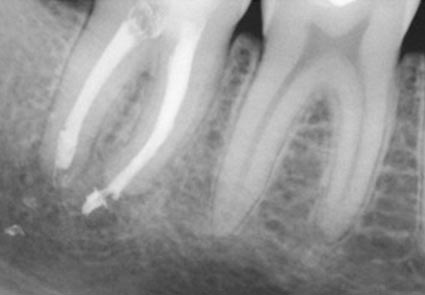

The greater the amount of uncleaned and unfilled canal space that remains after a root canal procedure, the greater failure rate. The challenge for clinicians is to decide to what point endodontic obturation should be directed in the given procedure. Cleaning, shaping and obturating less than the entire root canal space has the potential to or certainly could leave uncleaned and unfilled space, especially if the root is obturated to levels determined by arbitrary anatomic averages and not the true apical foramen.

Root canal overfills occur when a dentist is obturating (filling) a root canal. If the gutta percha(canal filling material) extrudes out the end of the root it is called an overfill. Sometimes, the gutta percha may have slipped through because it was not of sufficient diameter to bind at the apex. If a guttapercha that is too small is used, it can slip thru the tiny apical foramen (a hole at the tip of the root) and the resulting over fill may or may not form good seal . If the gutta percha does not adequately obturate (seal) the apex, then bacteria can repopulate any left over space. This bacterial colonization is most likely the actual cause of most endodontic failures associated with overfills.